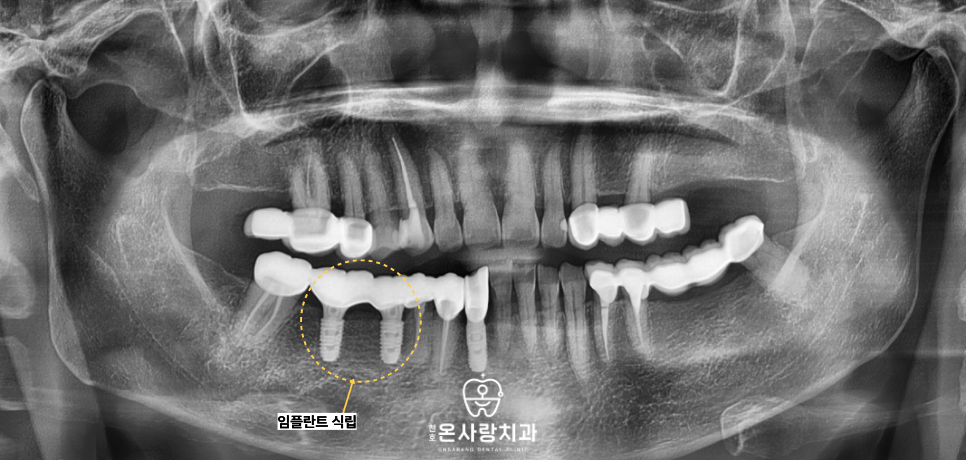

또한 기존에 치아가 비어 있던 자리에는

인공치아인 천호역임플란트를 식립함으로써

브릿지에만 의존하던 구조에서 벗어나

각 치아가 독립적으로 씹는 힘을

견딜 수 있도록 재구성하였습니다.